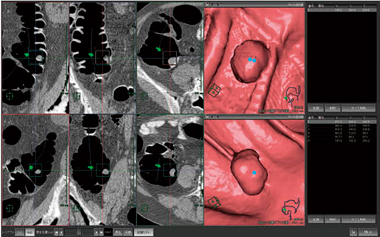

全自動処理機能では,最初のワンクリックで,大腸抽出から経路検索までを自動的に処理が可能である。また,2体位同時解析機能では,同時に2体位の画像解析が可能で,フルオートで解析処理を行ってくれる。さらに,2体位の画像を任意の位置で同期表示ができるなど,CT撮影で得られた情報を最大限に活用することが可能である。

図2 2体位同時解析機能